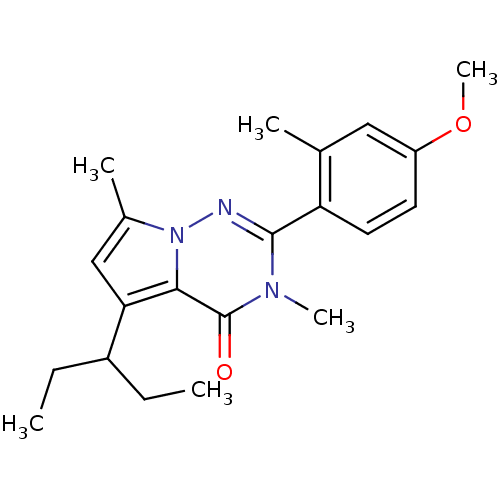

TargetCorticotropin-releasing factor receptor 1(Homo sapiens (Human))

Dupont Pharmaceuticals

Curated by ChEMBL

Dupont Pharmaceuticals

Curated by ChEMBL

Affinity DataEC50: 0.700nMAssay Description:Antagonist activity at human CRF1 receptor expressed in CHO-K1 cells assessed as inhibition of CRF-induced cAMP accumulation after 15 mins by cAMP en...More data for this Ligand-Target Pair

TargetCorticotropin-releasing factor receptor 1(Homo sapiens (Human))

Dupont Pharmaceuticals

Curated by ChEMBL

Dupont Pharmaceuticals

Curated by ChEMBL

Affinity DataEC50: 0.700nMAssay Description:Antagonist activity at human CRF1 receptor expressed in CHO-K1 cells assessed as CRF-stimulated cAMP accumulation by enzyme immunoassayMore data for this Ligand-Target Pair

Affinity DataEC50: 0.700nMAssay Description:Antagonist activity at CRF-R1 in mouse AtT-20 cells assessed as inhibition of human CRF induced cAMP accumulation after 30 mins by radioimmunoassayMore data for this Ligand-Target Pair

Affinity DataEC50: 0.800nMAssay Description:Antagonist activity at CRF-R1 in mouse AtT-20 cells assessed as inhibition of human CRF induced cAMP accumulation after 30 mins by radioimmunoassayMore data for this Ligand-Target Pair